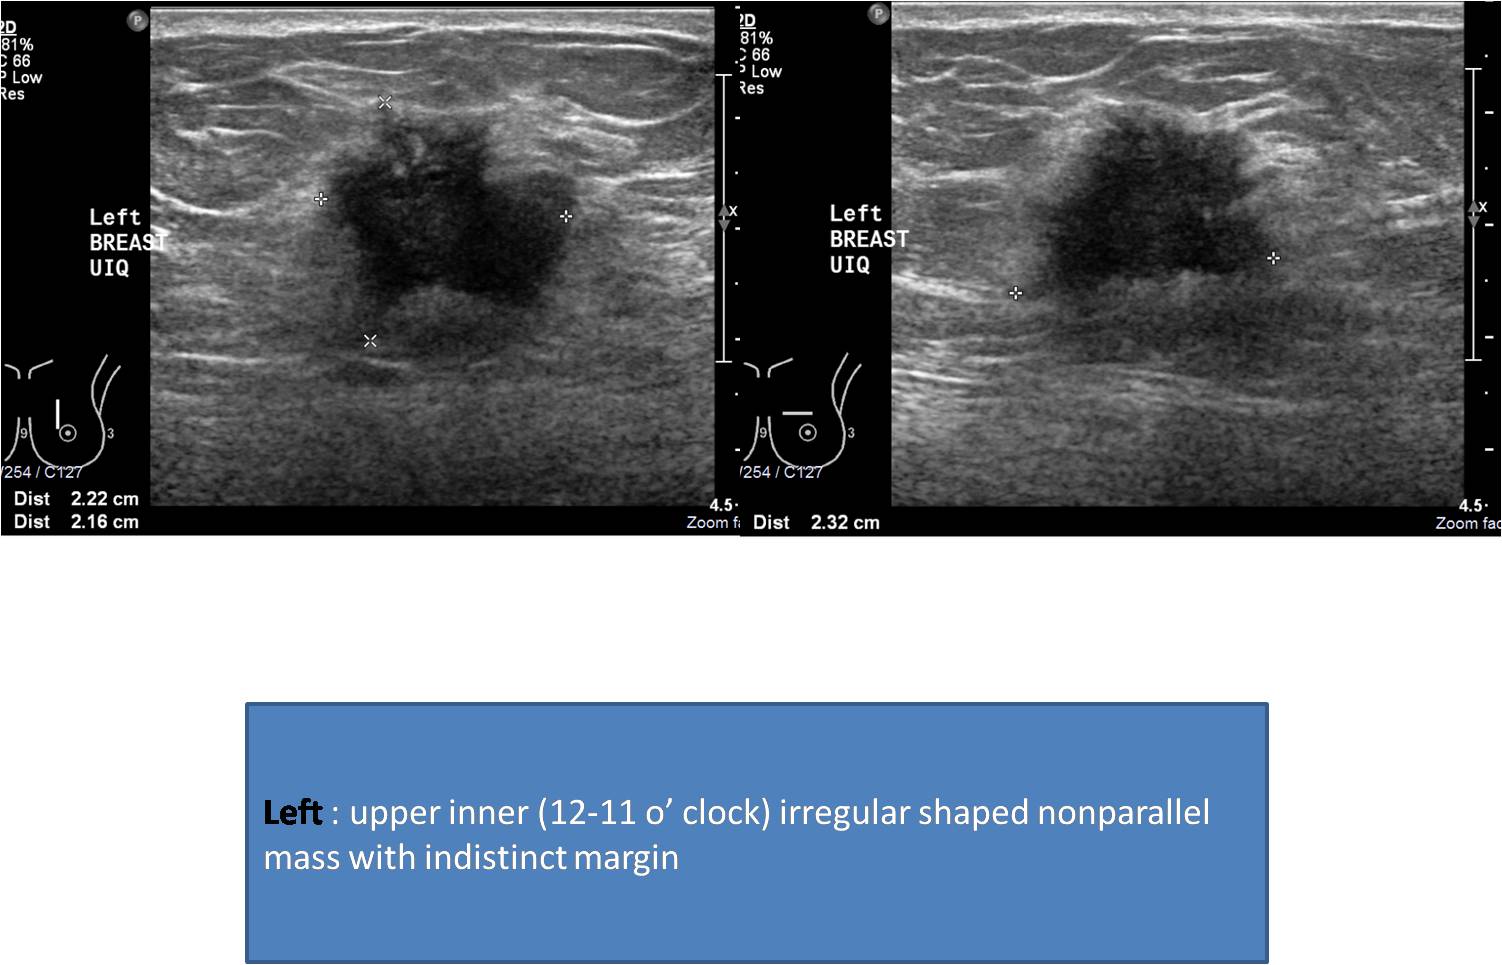

Mammography Right: upper central high density irregular shaped mass with spiculated margin. Nipple retracted. Left: upper central high density mass with spiculated margin. Nipple retracted. Ultrasound: findings described with images